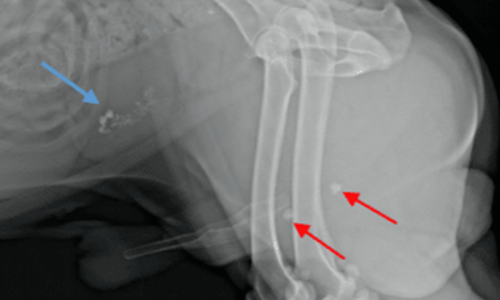

Ik probeer Simba te katheteriseren, maar de katheter blokkeert snel op een harde obstructie. Op een röntgenfoto zijn 2 urinestenen in de plasbuis en nog enkele in de blaas te zien.